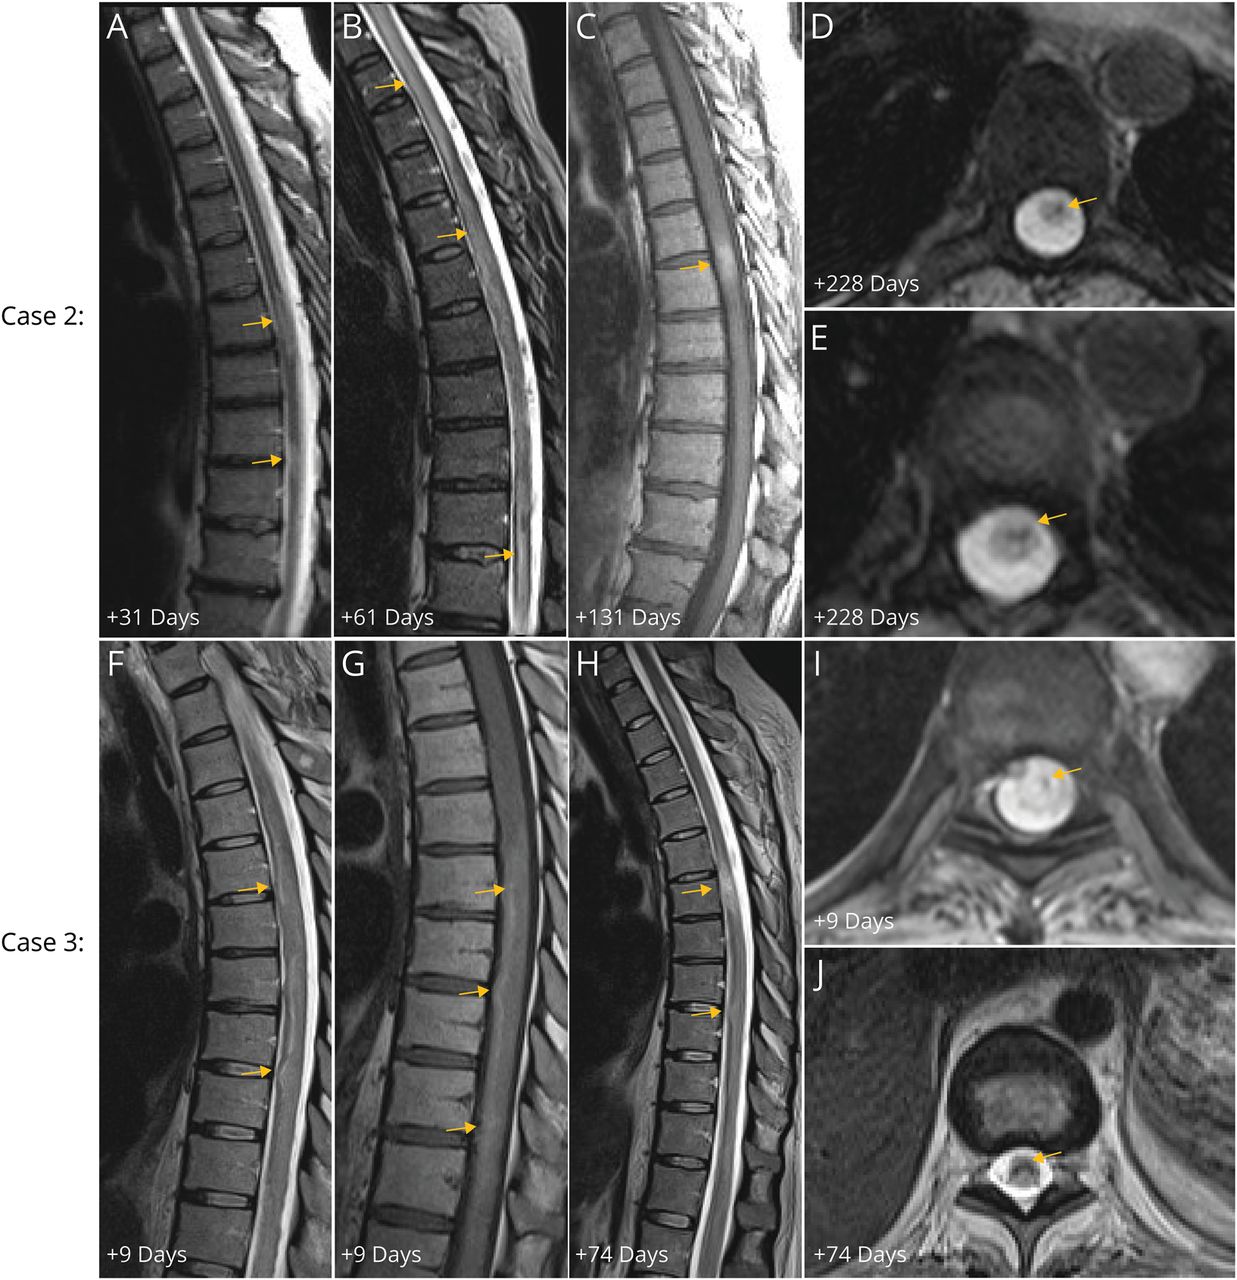

初始神经系统检查显示完整的功率、反射亢进和感官水平显示。脊柱MRI(1月后神经症状)显示膨胀性的t2加权hyperintensities T6-8和T9-10 (图2一个对比度增强。脑部核磁共振成像显示多个室和pericallosal nonenhancing t2加权病变。同一天CSF分析显示94红细胞/μL, 7白细胞/μL淋巴细胞(94%),32 mg / dL的蛋白质、免疫球蛋白升高指数(1.77),serum-unmatched脑脊液寡克隆乐队。脑脊液细菌染色和文化和病毒研究(巨细胞病毒(CMV)、带状疱疹和HSV)显示负面结果。艾滋病毒血清ANA, AQP-4免疫球蛋白,CBA的MOG免疫球蛋白抗体显示消极的结果。血小板、PT和APTT是正常的。她收到了1克IVMP每日3天。两周后,她于截瘫和尿潴留。出现症状后重复成像(9周)显示near-confluent进展的t2加权hyperintensity C2-L1 (图2 b对比度增强)和不完整的。她收到了5天的1 g IVMP和血浆置换和口服强的松锥形开始(60毫克每日,锥形每周10毫克)。她收到rituximab-pvvr。

面板展示了矢状t2加权图像显示轻度膨胀性的hyperintensity在中央线T6-T8和T9-T10(相应的对比度增强t1加权成像未显示)在31天,随后发展为融合性的扩张和中央t2加权hyperintensity从C2延伸至L1 61天(面板B)。面板C演示precontrast t1 hyperintensity对应区域的出血,也见证了电池板D和E,显示慢性血副产品在轴向t2加权快速二维角度拍摄的序列在228天。面板F演示了一个矢状t2加权图像在9天的广泛的膨胀性的线信号异常整个绳(T1圆锥)连同precontrast T1 hyperintensity面板g . Microhemorrhage演示了在轴向t2加权序列二维多次回声在面板:面板H 9天了多焦点的t2加权hyperintensity和膨胀性的中央线整个线有明显的外观异常的血液副产品涡轮旋转回声序列在面板上J。

重复t2加权成像在4个月显示改善hyperintensity和进化慢性出血在T6-T7 precontrast t1加权成像(图2 c)和轴向梯度回波。约8个月,她仍然截瘫的(= 5,夫人eds = 8.0),与解决precontrast t1 hyperintensity和血液副产品在t2加权快速二维角度拍摄的序列(图2中,D和E)。脊柱MRI在1年显示脊髓软化(T5-T9)。

一名26岁的妇女承认COVID-19心肌炎、心原性休克,multiorgan失败。十天的地塞米松有症状感染治疗的一部分。她接种adenovirus-vectored COVID-19疫苗(詹森生物技术)5个月前感染症状。四个星期进她的病,她急性提升感官损失,其次是弛缓性截瘫和无反射,达到最低点1周。演示的脑脊液神经症状(3天后)23红细胞/μL 3白细胞/μL嗜中性粒细胞(75%),36 mg / dL的蛋白质,与寡克隆。胸椎MRI(9天后神经症状)显示膨胀性的t2加权hyperintensity (T1本土precontrast T1 hyperintensity和microhemorrhage t2加权二维多次回声序列(图2中,F, G,和我)。主动脉造影是正常的。重复CSF分析(后19天前)显示2红细胞/μL, 1白细胞/μL淋巴细胞(55%),36 mg / dL的蛋白质,略高免疫球蛋白g指数(0.67)。传染病研究包括CSF HSV (PCR)、带状疱疹、巨细胞病毒和eb病毒血清学显示负面结果。血清HIV、安娜和CSF自身免疫性脑病自身抗体面板显示负面结果(梅奥诊所实验室)。血小板、PT和APTT是正常的。预防肝素皮下(每天两次5000单位)管理。血清AQP-4免疫球蛋白和MOG CBA的免疫球蛋白抗体显示消极的结果。她收到了5剂量的1 g IVMP(13天后神经症状),其次是口服强的松锥(每天40毫克,锥形每周10毫克)。重复成像在2个月显示持续的t2加权hyperintensity和出血涡轮旋转回声序列(图2中,H和J)。在5个月,她仍然截瘫的(= 5,夫人eds = 8.0)。